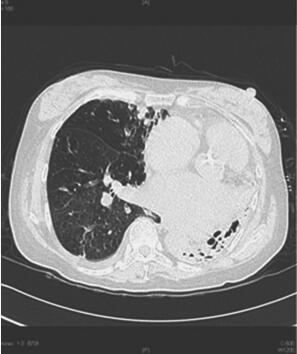

1小时条评论【病情介绍】 患者,女性,60岁。因咳嗽、咳痰10年,气促2年,水肿半月,加重3天于2011年4月7日入急诊病房。10年前间断出现咳嗽、咳痰,间歇给予静脉用药,每月1~3次。5年前再发,伴咯血,于笔者医院呼吸科住院治疗,诊断为支气管扩张,出院后长期口服大环内酯类抗...